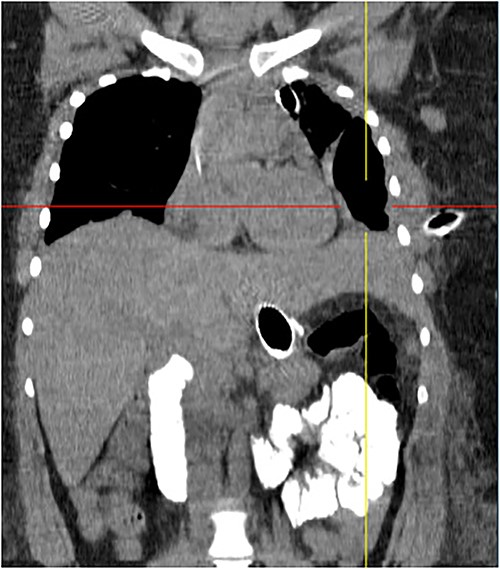

On 19 January 2021, a tomographic control showed leakage from the esophagogastric junction and left-sided pneumonia (Figs 4 and 5). Consultation with the cardiothoracic surgery department led to the decision to perform VATS.

Chest tomography revealing the presence of left pleural fluid and cavitations.

Coronal chest tomography showing the presence of the gastroesophageal stent and the left pleurothoracic cavity.